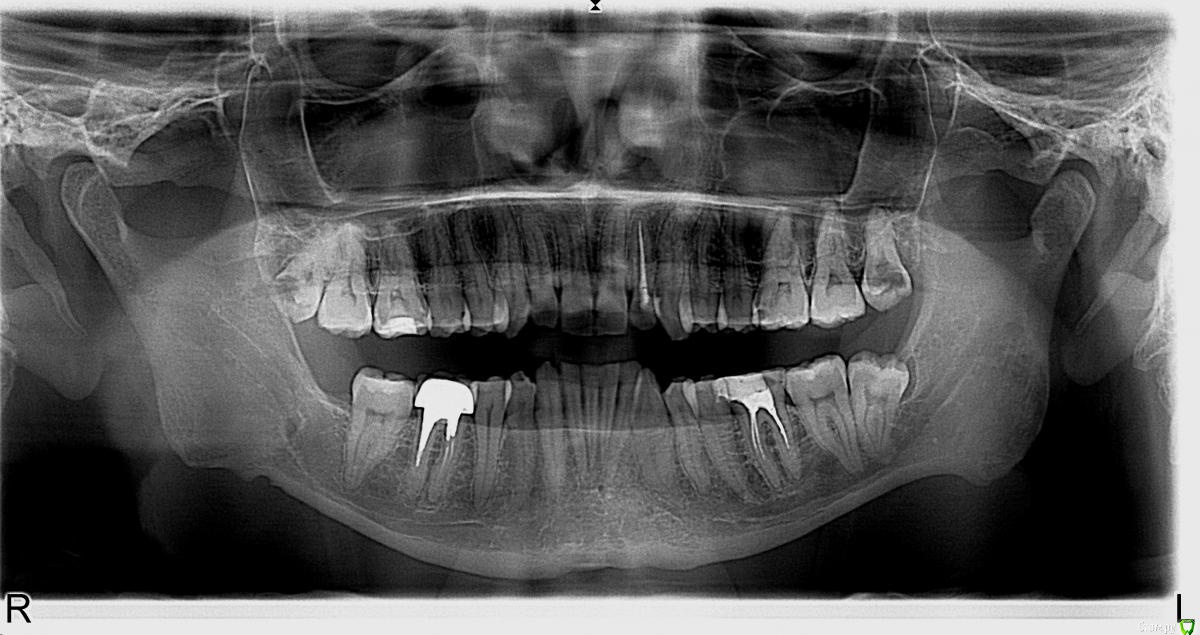

St. Опубликовано 3 декабря, 2015 Автор Поделиться Опубликовано 3 декабря, 2015 Пациентка, 28лет. Зуб ранее лечен по поводу неосложненного кариеса около 8 лет назад, пломба состоятельная. Полгода назад на ОПГ обнаружен очаг разрежения, свищ по переходной складке. Субъективно жалоб не было. Сделали КТ. Обсудили возможности и риски эндо.Пациентка согласилась попробовать консервативное лечение, но только позже. В первый визит свищ с экссудатом, перкуссия слабо положительная. Открыли, трещин нет, каналы широкие, некротические массы, специфический запах. ПроТейперы Ф1, апикально 35.02 .Медобработка гипохлорит(+ у/з), эдта. Кальций. Временная пломба. Через 10 дней симптоматики нет, экссудата из свища нет, однако свищ сохраняется.Ещё раз мех и мед обработка. Гидроокись. Пациентка уехала на месяц. Визит третий. Свищ закрылся. Перкуссиб б/б.Расширила апикально до 45.02. Мед.обработка гипохлорит, ЭДТА, перекись, хлоргексидин 2%. Латералка. Ждем что будет через 6 мес. 1 Ссылка на комментарий

St. Опубликовано 22 декабря, 2015 Автор Поделиться Опубликовано 22 декабря, 2015 Немножко фейл... Надо таки было МТА закрывать, хотя и четкий апикальный упор был. 2 Ссылка на комментарий

DmitrySH Опубликовано 22 декабря, 2015 Поделиться Опубликовано 22 декабря, 2015 Анастасия, да протолкнули герметик, но ничего ужасного от этого не произойдет. Мне вот на финальном снимке интересно, это не трещина? Ссылка на комментарий

St. Опубликовано 22 декабря, 2015 Автор Поделиться Опубликовано 22 декабря, 2015 (изменено) Нет, это у нас со снимками беда.. По твердым тканям всё гуд. С силлером перебор случился. А пациентка вообще несчастливая. 47 уже удалили. Изменено 22 декабря, 2015 пользователем St. Ссылка на комментарий

St. Опубликовано 26 декабря, 2015 Автор Поделиться Опубликовано 26 декабря, 2015 В продолжение темы из поста №17 http://forum.stom.ru/topic/29857-endo/?p=509407. Трещин не нашли, зато латеральку обнаружили В устье и апексе достаточно плотная РФП, в середине вообще было пусто. 6 Ссылка на комментарий